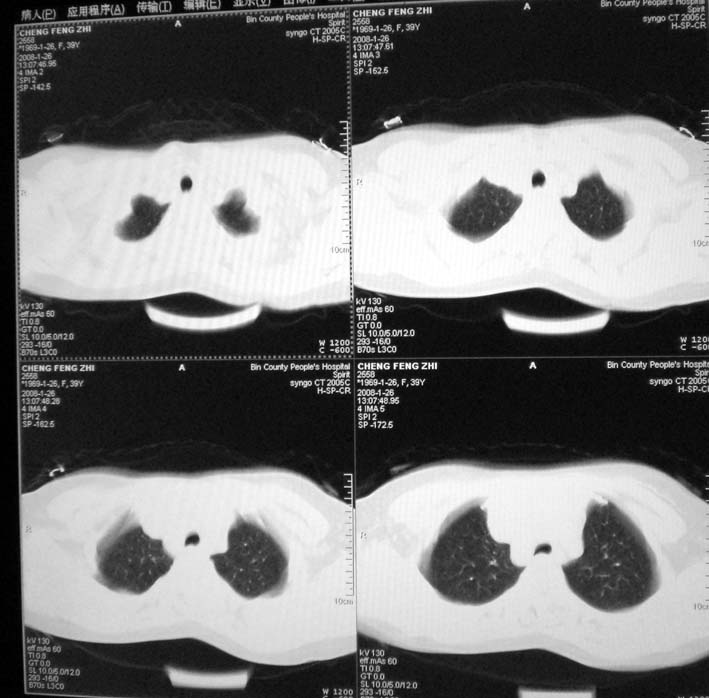

以下是引用guoke在2008-1-27 14:15:00的发言:[br]纵隔增宽,纵隔内血管境界不清,心包积液,考虑纵隔淋巴瘤.[br]

以下是引用随光逐影在2008-1-27 15:52:00的发言:[br]1)考虑为:淋巴瘤。建议:行进一步检查。2)心包积液。